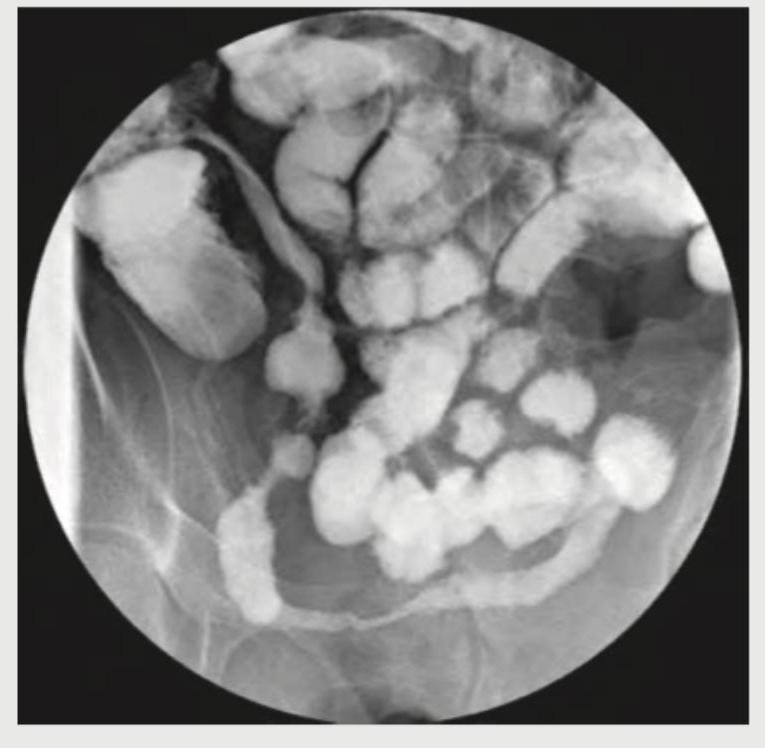

The following X-ray abdomen is diagnostic of:

Explanation: ***Cobblestone appearance*** - The image shows a **barium study** of the small bowel, revealing an irregular, nodular mucosal pattern, which is characteristic of the **cobblestone appearance**. - This appearance is typically seen in **Crohn's disease** due to deep ulcerations crisscrossing with edematous, inflamed mucosa. - The combination of **linear ulcers** and **transverse fissures** separated by areas of edematous mucosa creates this distinctive pattern. *Belt sign* - The **belt sign** is a radiological finding on **CT imaging** associated with **blunt abdominal trauma**, particularly **seat belt injuries**. - It refers to bowel wall thickening, mesenteric hematoma, or abdominal wall bruising in the distribution of a seat belt. - This sign is not observed in the gastrointestinal barium study pattern shown in this image. *String sign* - The **string sign** is also seen in Crohn's disease but refers to a **severely narrowed or stenotic bowel lumen**, appearing as a thin, continuous string of barium. - This occurs due to chronic inflammation leading to fibrotic strictures. - While Crohn's can cause both findings, the image prominently displays the nodular, irregular mucosal pattern rather than a simple string-like narrowing. *Coffee bean sign* - The **coffee bean sign** is a classic radiographic finding in **sigmoid volvulus** on plain abdominal X-ray. - A massively dilated, gas-filled loop of bowel creates an appearance resembling a coffee bean. - This sign is distinct from the intestinal mucosal pattern observed in the provided barium study.